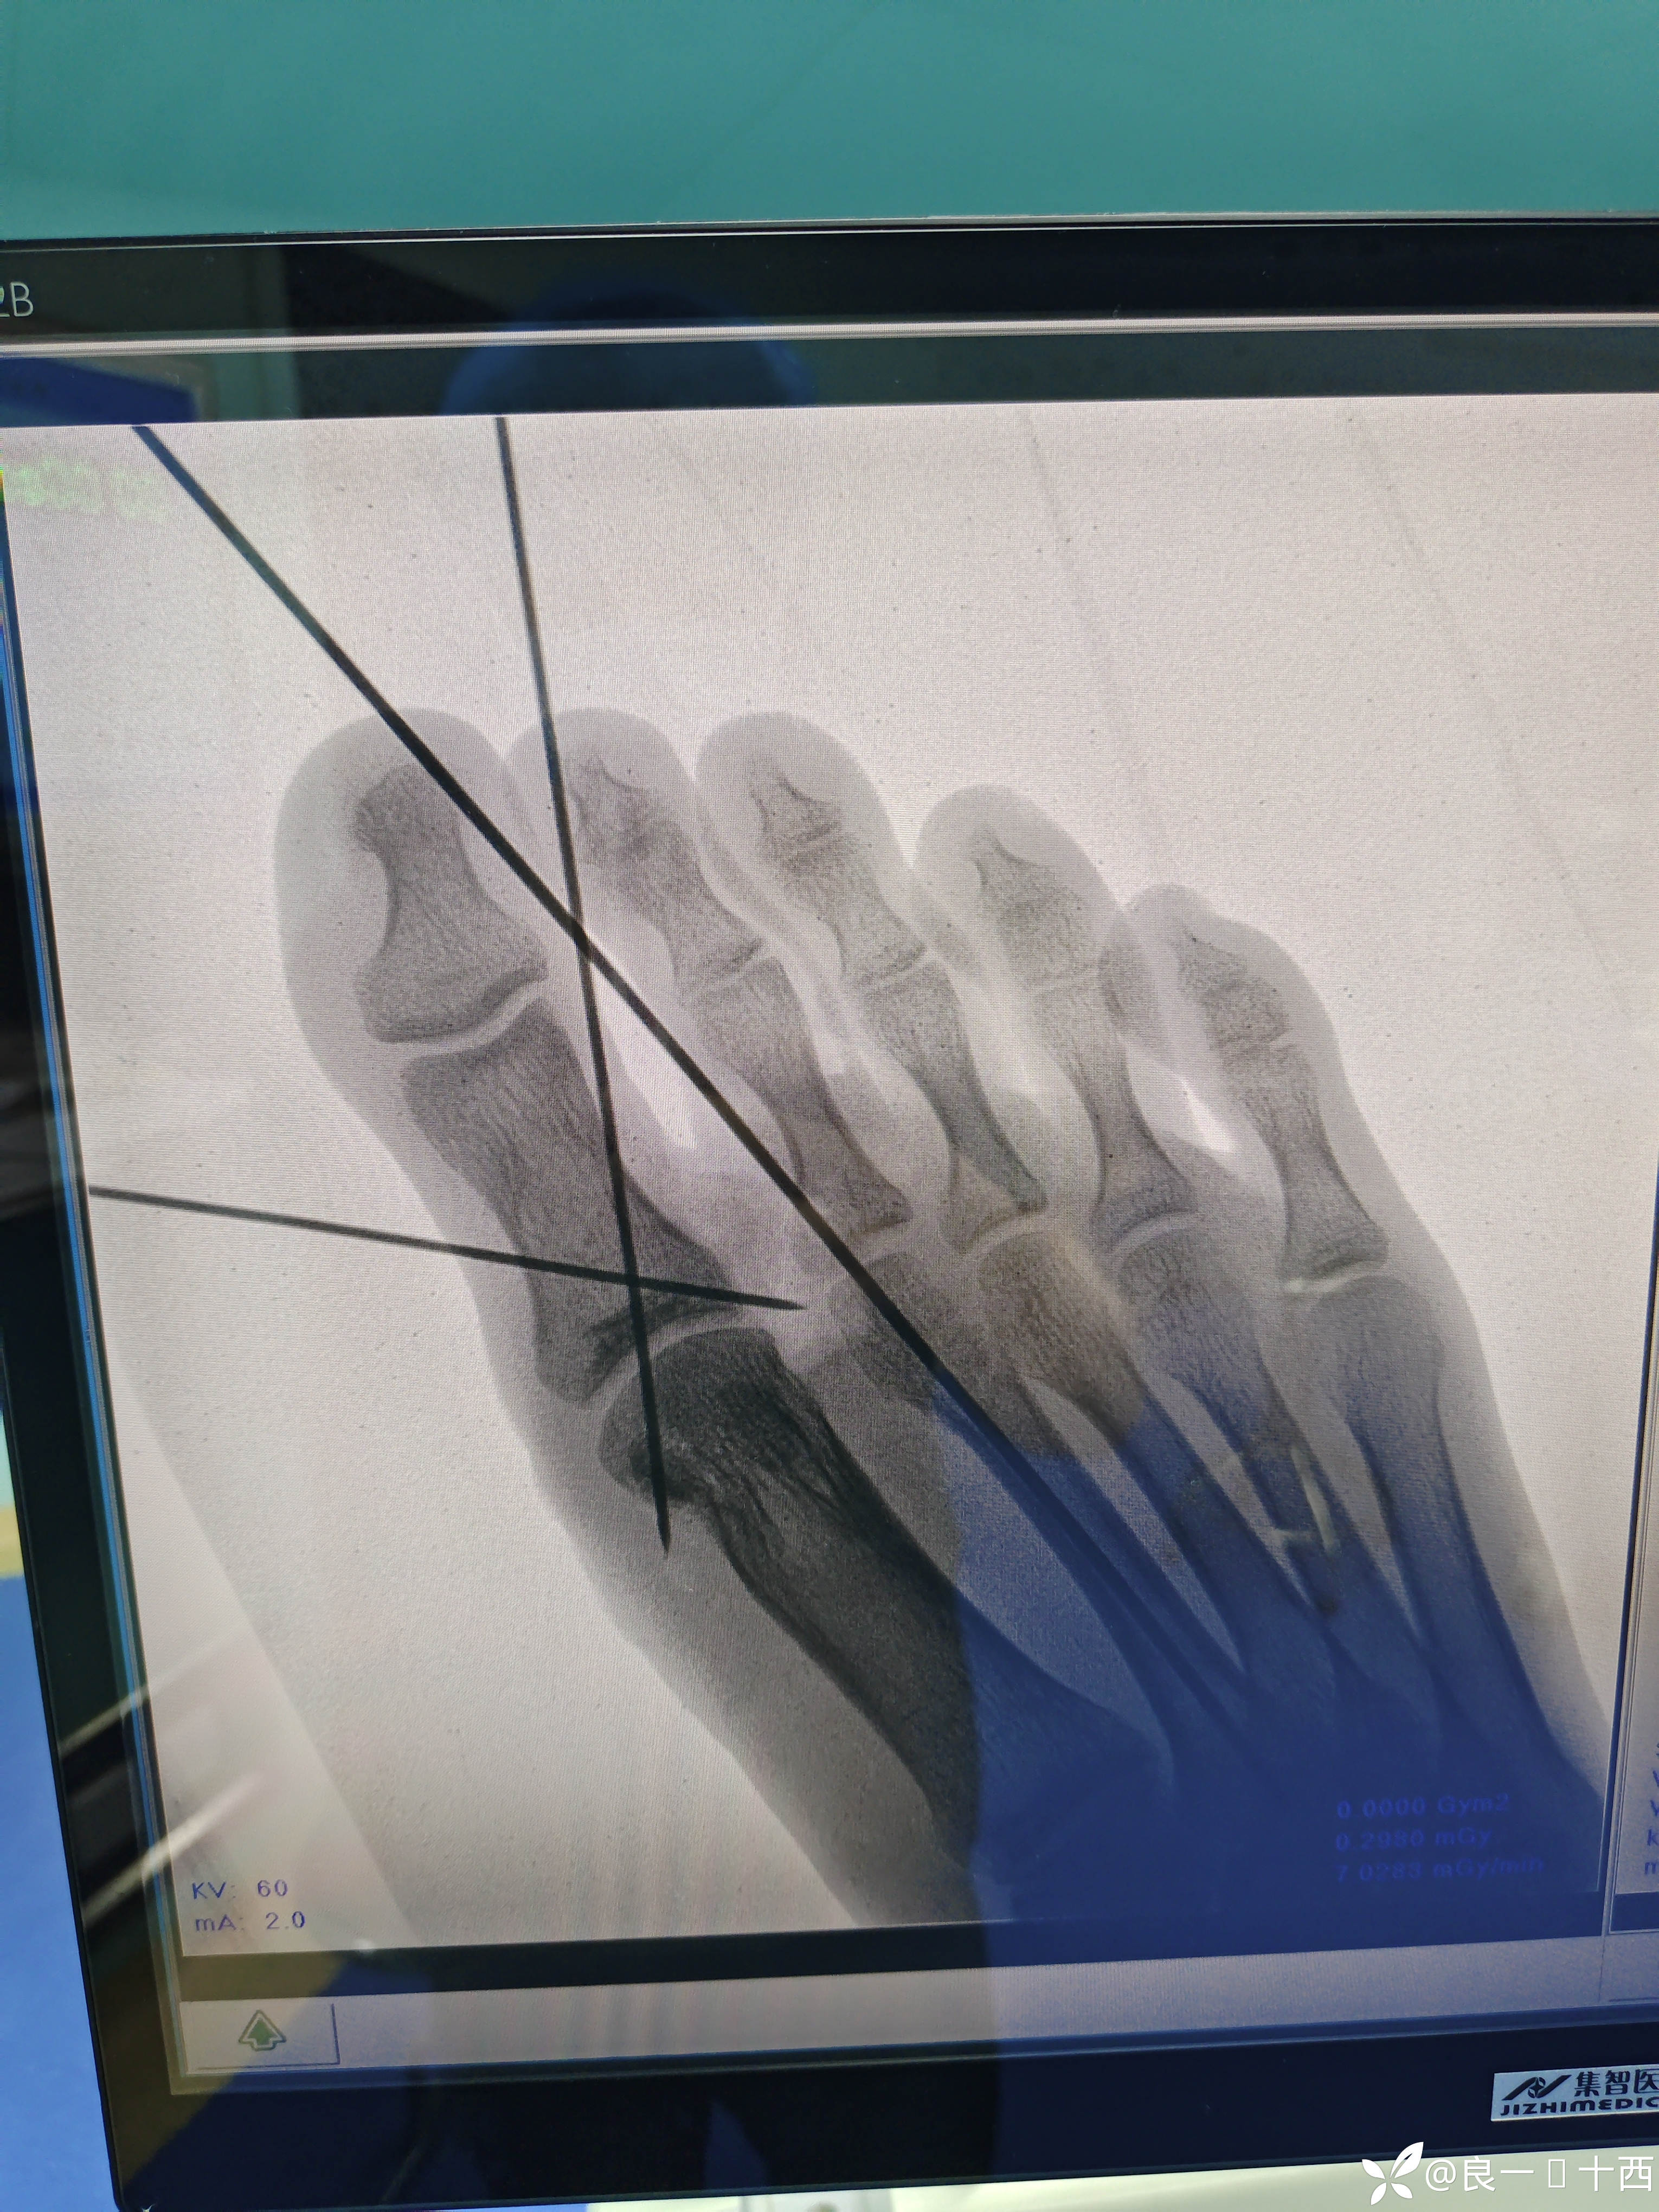

一位18岁帅气少年,应该是晚上通宵上网了,回来时候精神状态不佳,导致自己骑车出了车祸。初步检查后,得出诊断如下,右足拇趾基底部开放性撕脱骨折,拇收肌横头撕脱,第一跖趾关节开放性脱位,第二跖骨头开放性骨折,右足背内侧撕脱伤